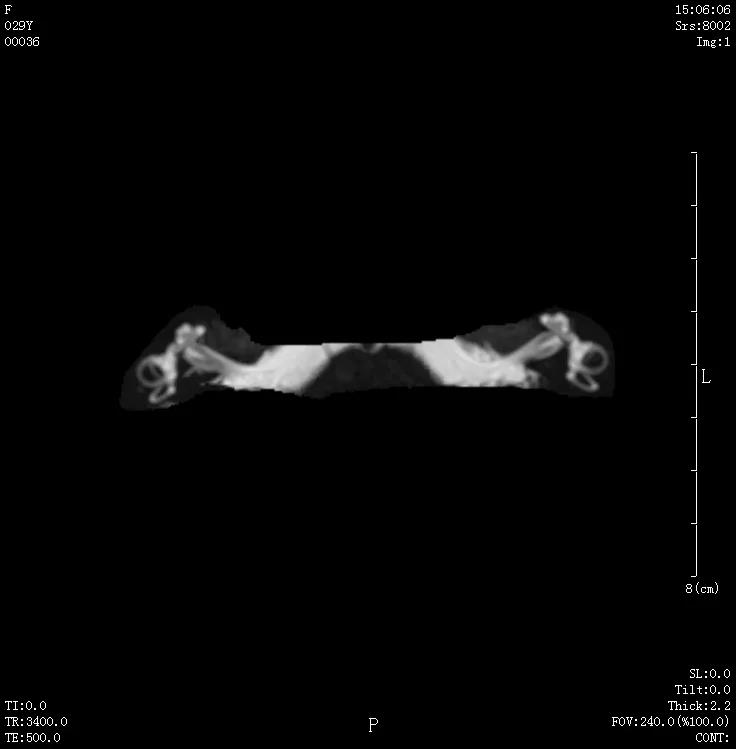

09 颈部血管成像,清晰显示颈部血管。